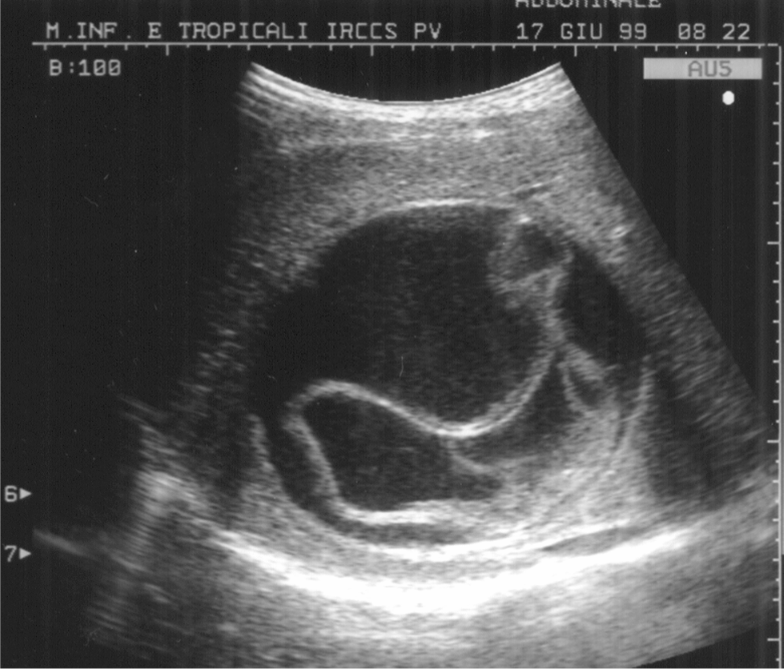

Galleria foto - Verme solitario, come riconoscerlo e contrastarlo Foto 2